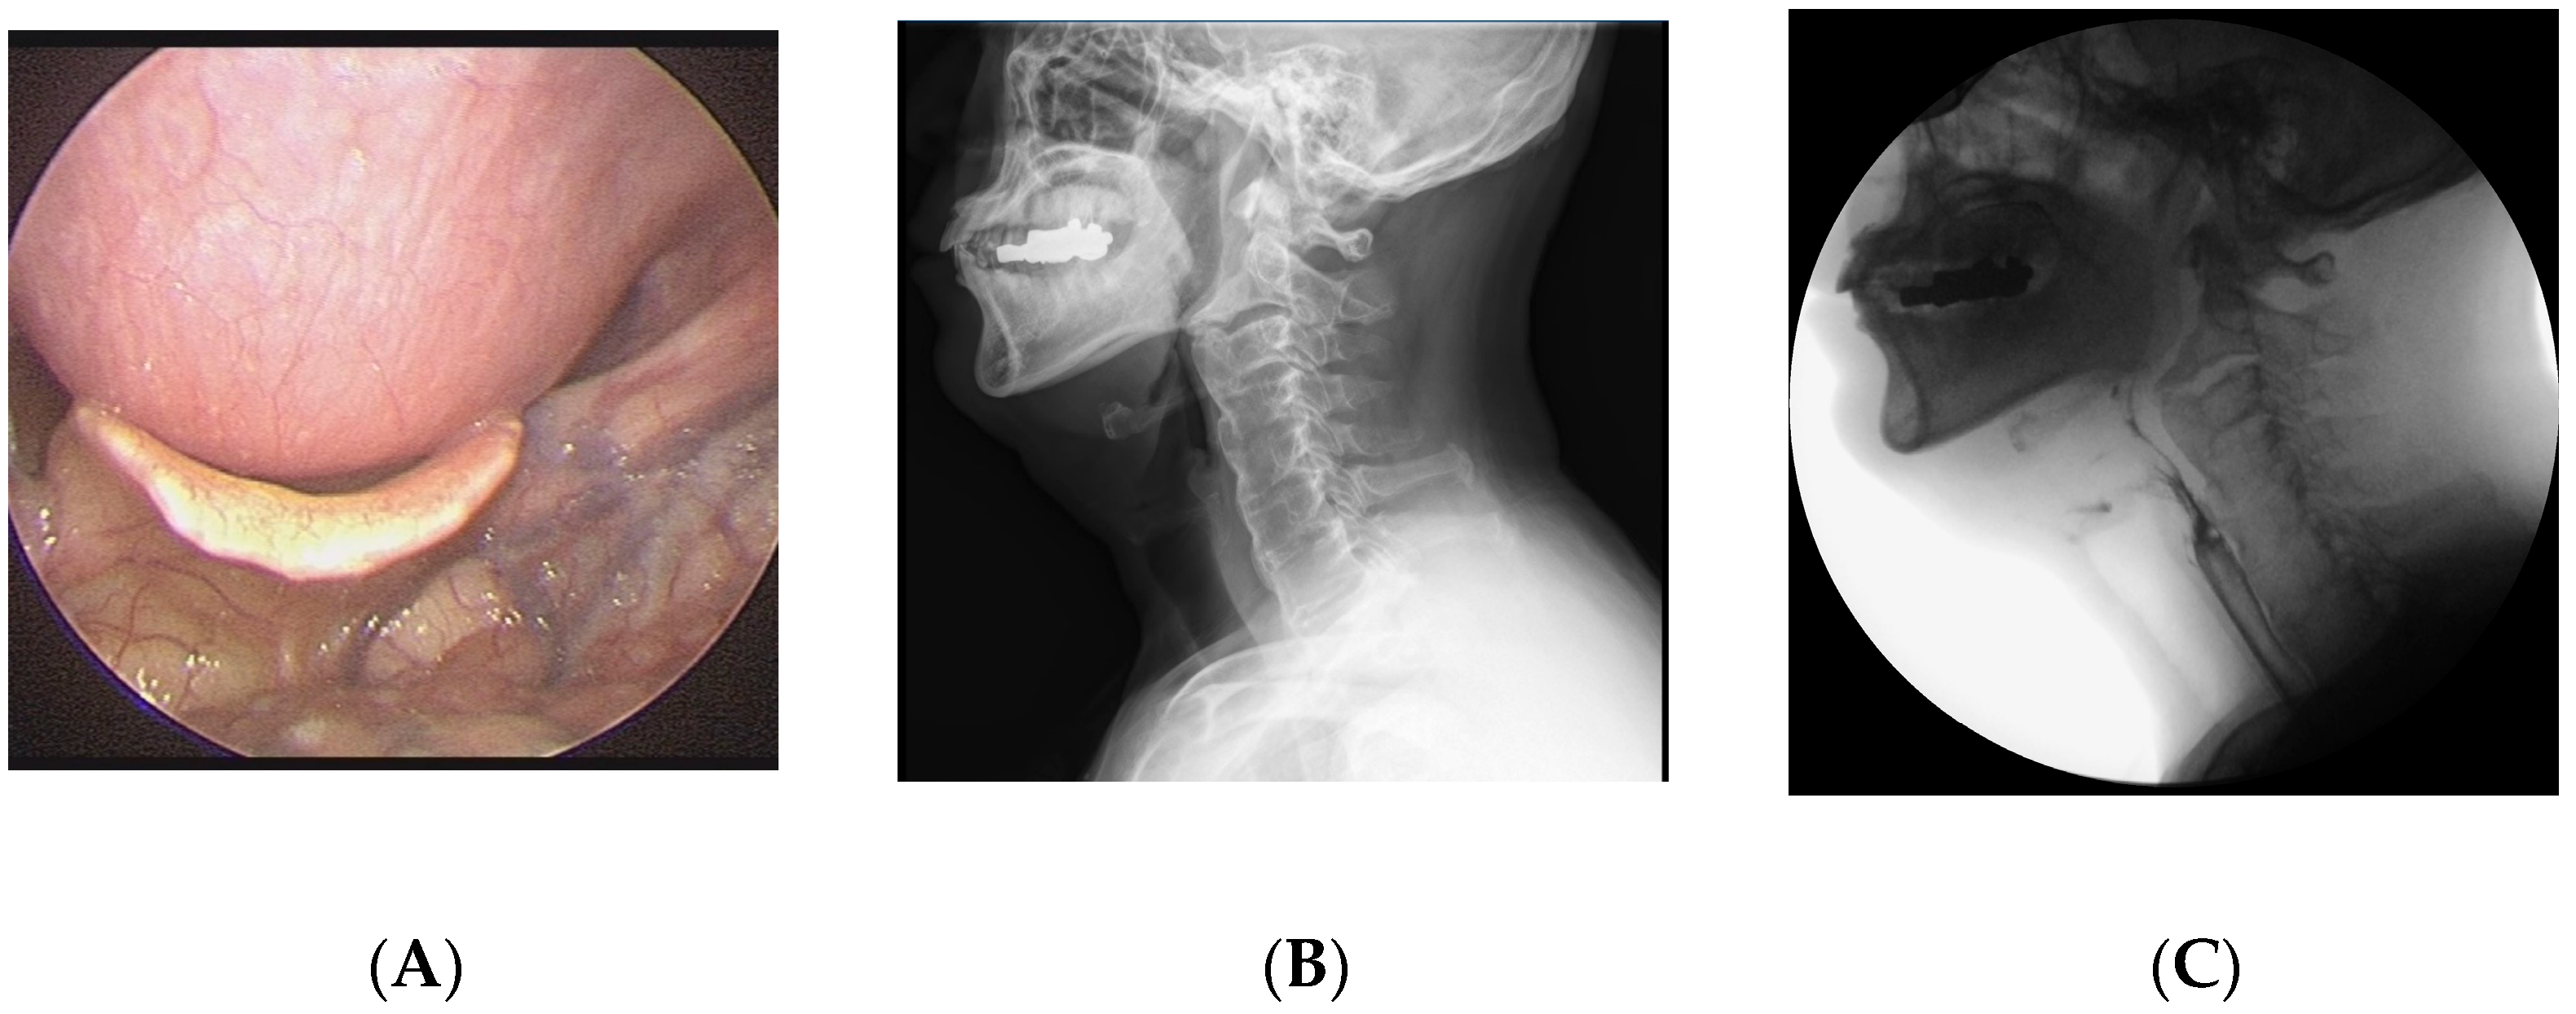

2.1. Case 1

2.2. Case 2